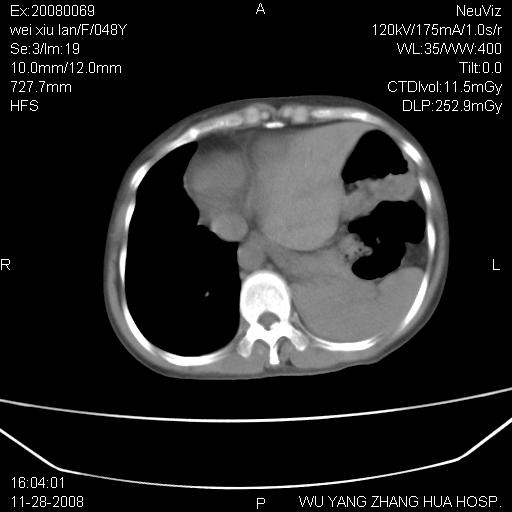

标题: CT16847:女,48岁,咳嗽,发热两日,平常偶有上腹部不适。 [打印本页]

标题: CT16847:女,48岁,咳嗽,发热两日,平常偶有上腹部不适。

能否考虑食管裂孔疝?请老师们多多指教。

这个是左侧膈膨升伴不完全性胃翻转,手术将松弛的左横膈膜折叠缝合即解决问题。

支持左侧膈疝,心脏受压右移.

胃、脾脏及部分肠管明显升高,并压迫心脏移位,

首先考虑:左侧膈疝。

左侧胸腔内见胃肠及脾脏影

支持膈疝

左膈顶及肋膈角均上移,膈面光滑,考虑左膈肌麻痹